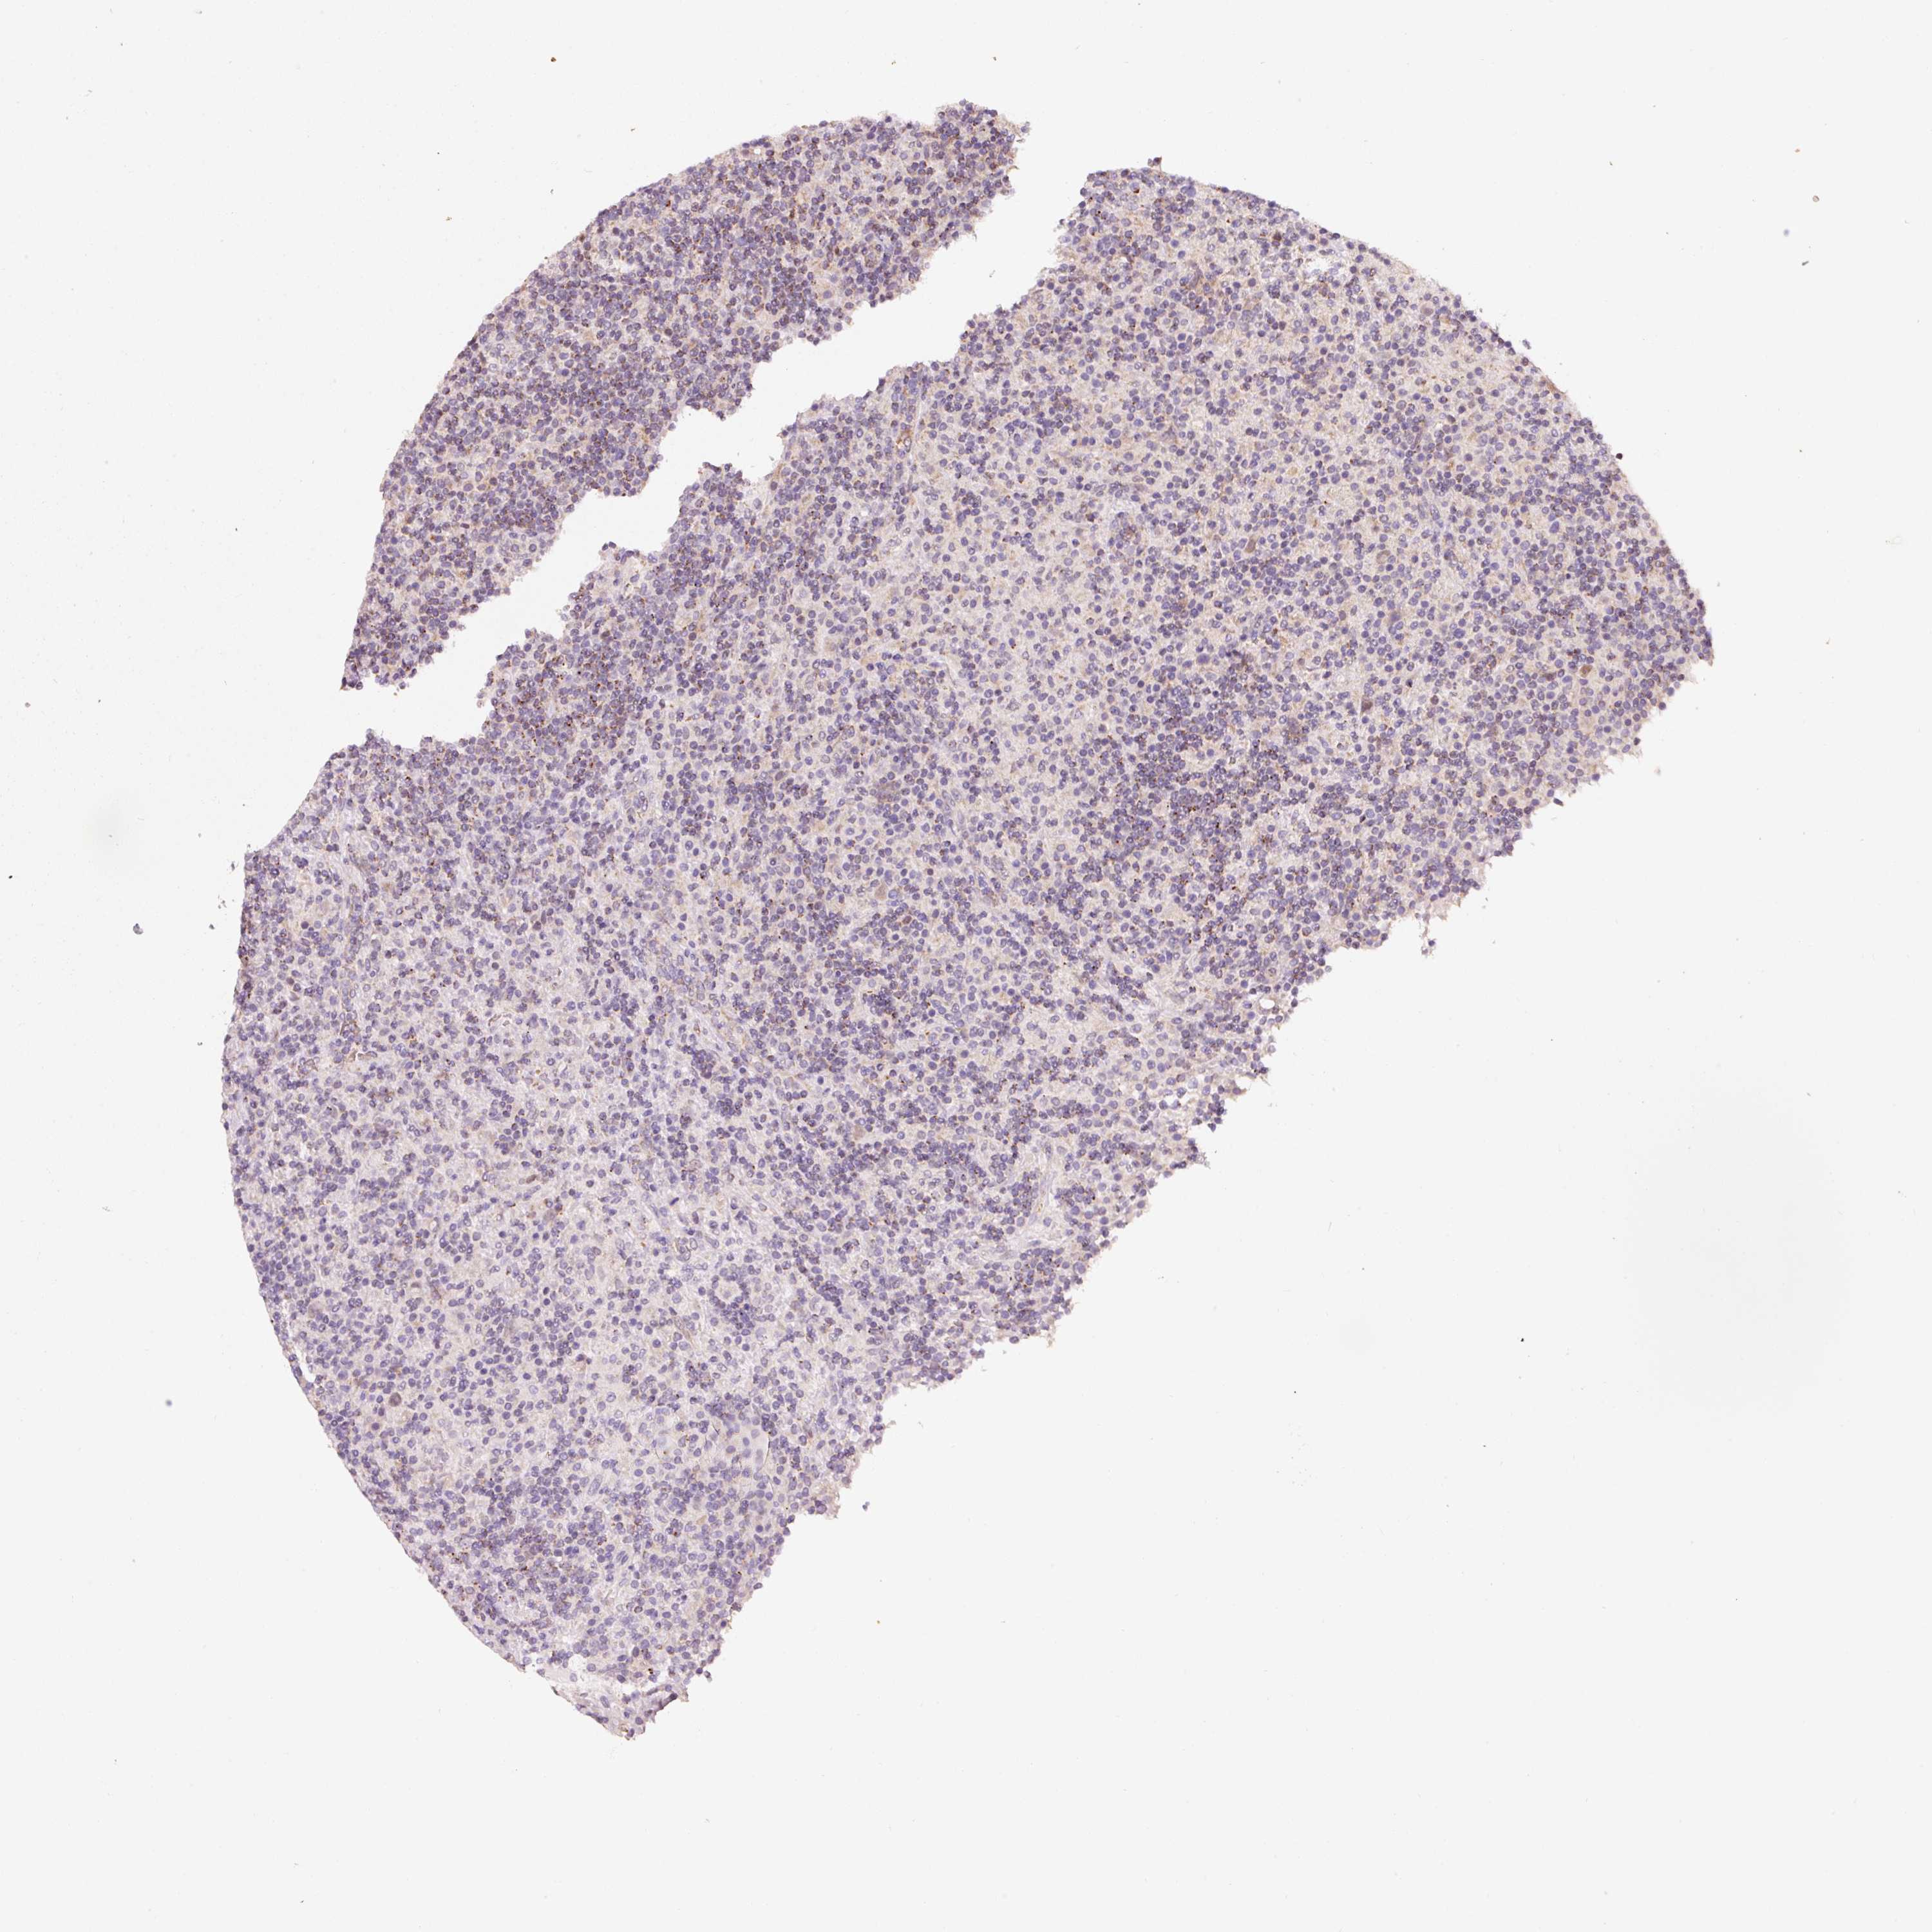

CANCER LYMPHOMA Show tissue menu

LYMPHOMA - Protein expressioni

A mouse-over function shows sample information and annotation data. Click on an image to view it in a full screen mode. Samples can be filtered based on level of antibody staining by selecting one or several of the following categories: high, medium, low and not detected. The assay and annotation is described here.

Each image is clickable and will lead to virtual microscopy that enables deeper exploration of all samples and also displays staining intensity scores, fraction scores and subcellular localization as well as patient and tissue information for each sample.

Antibody HPA053004

Staining

High

Medium

Low

Not detected

Intensity

Strong

Moderate

Weak

Negative

Quantity

>75%

75%-25%

<25%

None

Location

Nuclear

Cytoplasmic/membranous

Cytoplasmic/membranous,nuclear

Hodgkin's disease, NOS

Malignant lymphoma, non-Hodgkin's type, High grade

Malignant lymphoma, non-Hodgkin's type, Low grade